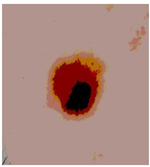

![]() | ![]() | ![]() | ![]() |

| Img1 | --- Pixel Intensity (0–255) ---> | ||

| Original Image | Th2 | Th3 | Th4 | Th5 |

|---|---|---|---|---|

![]() Img1 | ![]() | ![]() | ![]() | ![]() |